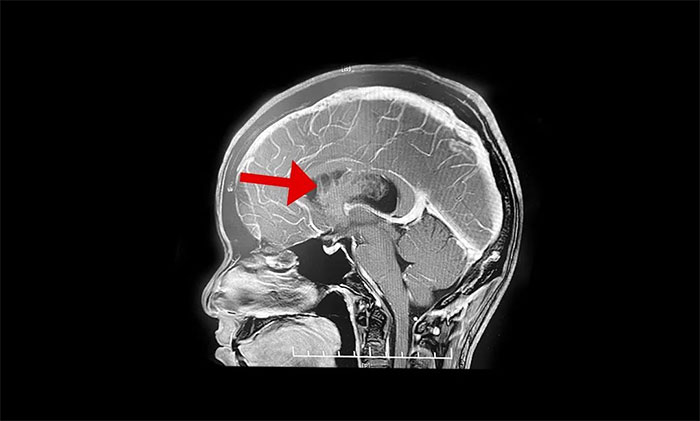

最終被診斷為中樞神經(jīng)細胞瘤。中樞神經(jīng)細胞瘤屬于比較罕見的腦腫瘤,一般直徑超過三公分即為巨大腫瘤,而李威腦室內(nèi)的腫瘤直徑竟達七公分,接近一個拳頭大小。幸運的是,順利手術(shù)切除。

上海藍十字腦科醫(yī)院神經(jīng)外科李士其教授介紹,中樞神經(jīng)細胞瘤(Central neurocytoma,CN)是少見的神經(jīng)系統(tǒng)腫瘤,1982年由Hansson首次報道并命名,2016年WHO神經(jīng)系統(tǒng)腫瘤組織學分類將其歸類為神經(jīng)元和混合型神經(jīng)元膠質(zhì)瘤(WHOⅡ級)。中樞神經(jīng)細胞瘤僅占顱內(nèi)腫瘤的0.25%~0.50%,好發(fā)于20~40歲青年人,無性別差異。病史一般較長,可達數(shù)十年之久,好發(fā)于側(cè)腦室透明隔,當病變累及Monro孔時,阻塞腦脊液循環(huán),引起頭痛、頭暈、惡性、嘔吐以及不同程度視力改變等非特異性顱內(nèi)高壓癥狀。

李士其教授介紹,該腫瘤一般生長于側(cè)腦室或三腦室,由于生長的位置處于腦室內(nèi),有較大空隙代償,疾病初期癥狀并不典型,當出現(xiàn)如頭痛、嘔吐等臨床癥狀時,瘤體已經(jīng)比較大。在治療上首先建議進行手術(shù)切除,解除腫瘤占位效應,通暢腦脊液通路,緩解腦積水,解除顱內(nèi)高壓。李士其教授指出,中樞神經(jīng)細胞瘤一般為偏良性腫瘤,若能手術(shù)全切腫瘤,或者大部分切除后輔助放療可以長期生存。所以,手術(shù)這一步非常關鍵。

▲ 非典型性中樞神經(jīng)細胞瘤

但由于腫瘤較大、血供豐富,且與腦室壁黏連明顯,致使腫瘤分離及切除異常困難。而且腦室內(nèi)血管及神經(jīng)組織結(jié)構(gòu)復雜、功能重要,如何在切除腫瘤的同時盡可能保護腦功能是手術(shù)的最大難點。